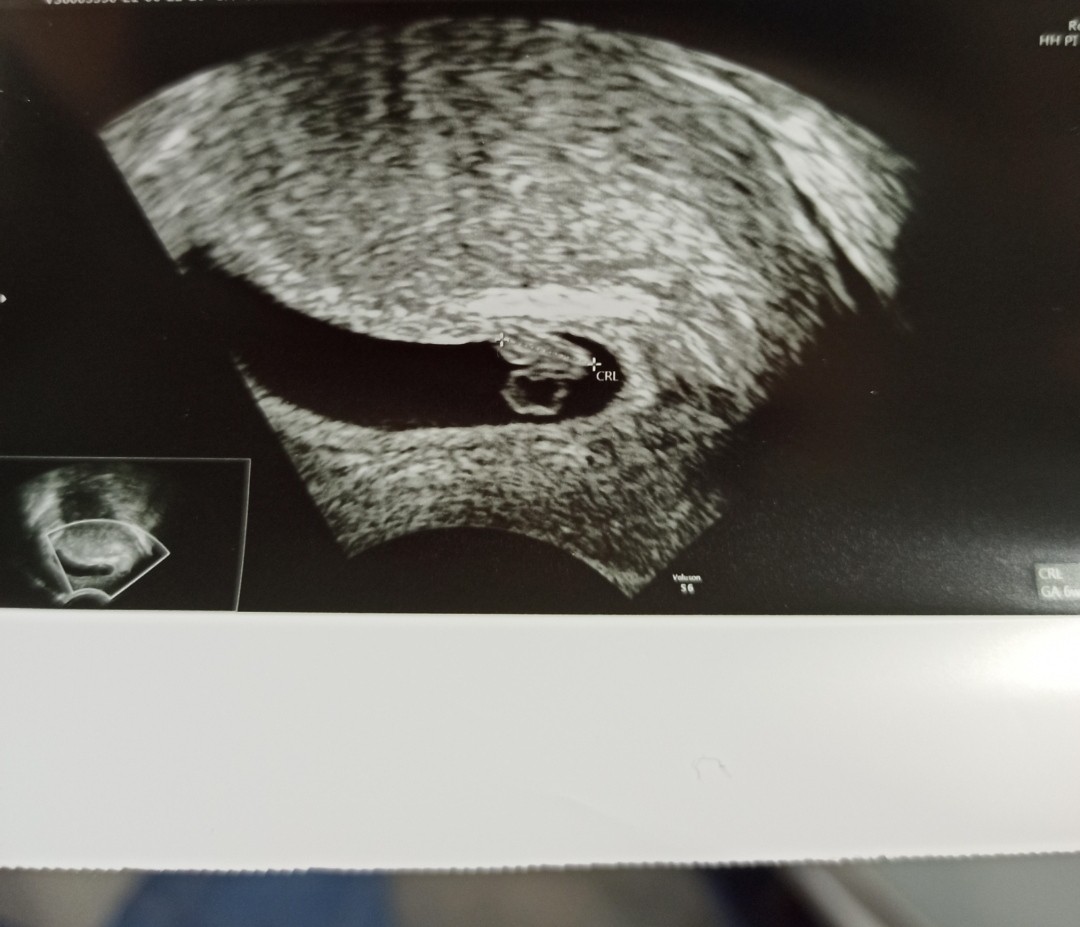

Właśnie wróciłam do domu, według USG 6+4, 6,6mm - tydzień młodsza ciąża niż liczona od OM. Kropka widać, serduszko pracuje. 👍

Załączniki

• IMG_20210622_185625.jpg

IMG_20210622_185625.jpg

133,9 KB · Wyświetleń: 125